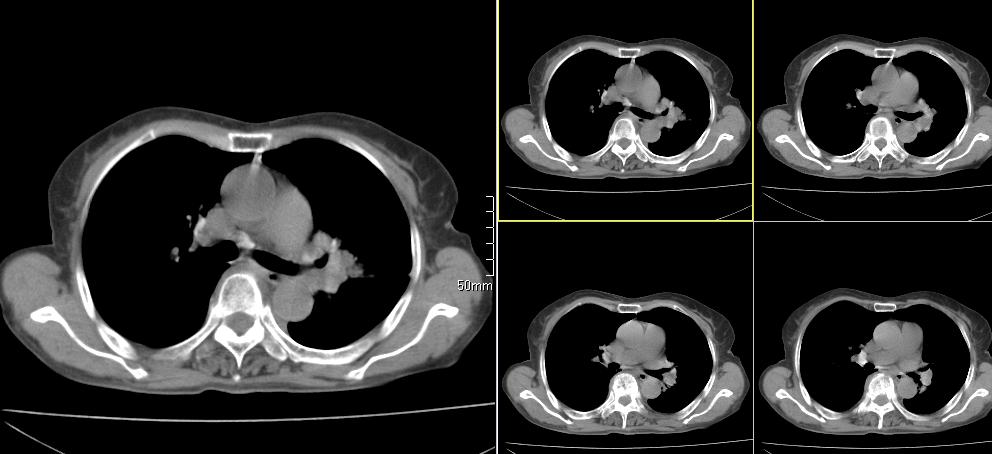

标题: CT26857:女,60岁,胃部不适前来就诊,不咳嗽,乏力,胸椎 [打印本页]

1、胸椎有骨质破坏伴周软组织,考虑胸椎转移。2、考虑左肺上叶尖后段支气管开口区周围型肺癌可能。

1、胸椎有骨质破坏伴周软组织,考虑胸椎转移。2、考虑左肺上叶尖后段支气管开口区周围型肺癌可能。建议行纤支镜检查!

1、胸椎有骨质破坏伴周软组织,考虑胸椎转移。2、考虑左肺中央型肺癌可能。

椎体有高密度影,多系转移。

1)考虑左肺中央型肺癌。2)胸椎转移瘤不排除;建议行mri检查。